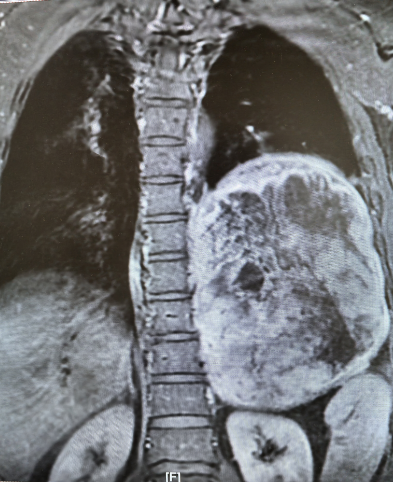

近日,北京天坛医院胸外科团队在多学科协作下,历经4小时,成功为患者完整切除左侧胸腔内直径近19厘米的巨大神经鞘瘤。此次手术的顺利完成,不仅彰显了北京天坛医院胸外科的精湛技术,更体现了多学科协作在疑难重症救治中的关键作用。

家中“顶梁柱”的杜先生,两个月前,左侧卧位时频繁出现心慌、胸痛等症状,当地医院检查后发现,其左后纵隔-胸腔内存在巨大占位性病变。进一步穿刺活检提示为“梭型细胞瘤,结合免疫组化考虑神经鞘瘤”,当地医院虽为其进行了射频消融治疗,暂时缓解了症状,但因肿瘤体积过大、位置特殊,手术切除难度极高,无法开展根治性治疗。

为寻求一线生机,杜先生通过熟人介绍并结合网上查询,慕名找到北京天坛医院胸外科主任医师杨增。医院胸CT检查结果令人揪心,成年人一侧胸腔宽度大约10-15厘米,而杜某的肿瘤直径近19厘米,占据了左侧多半个胸腔,把心脏和主动脉都挤偏了,原本竖直的主动脉已经弯到了右侧。再继续发展,一旦压迫到降主动脉,就会引发急性心衰,随时可能猝死。但更棘手的是,如果进行手术,该肿瘤为实性肿瘤,无任何囊变,血运极其丰富,且与左肺下叶致密粘连,甚至可能累及脊髓,手术中稍有不慎就可能导致心脏骤停、心律失常、大出血、截瘫等严重并发症。“不能因为风险高就放弃患者。”杨增了解情况后,当即决定将患者收入院。